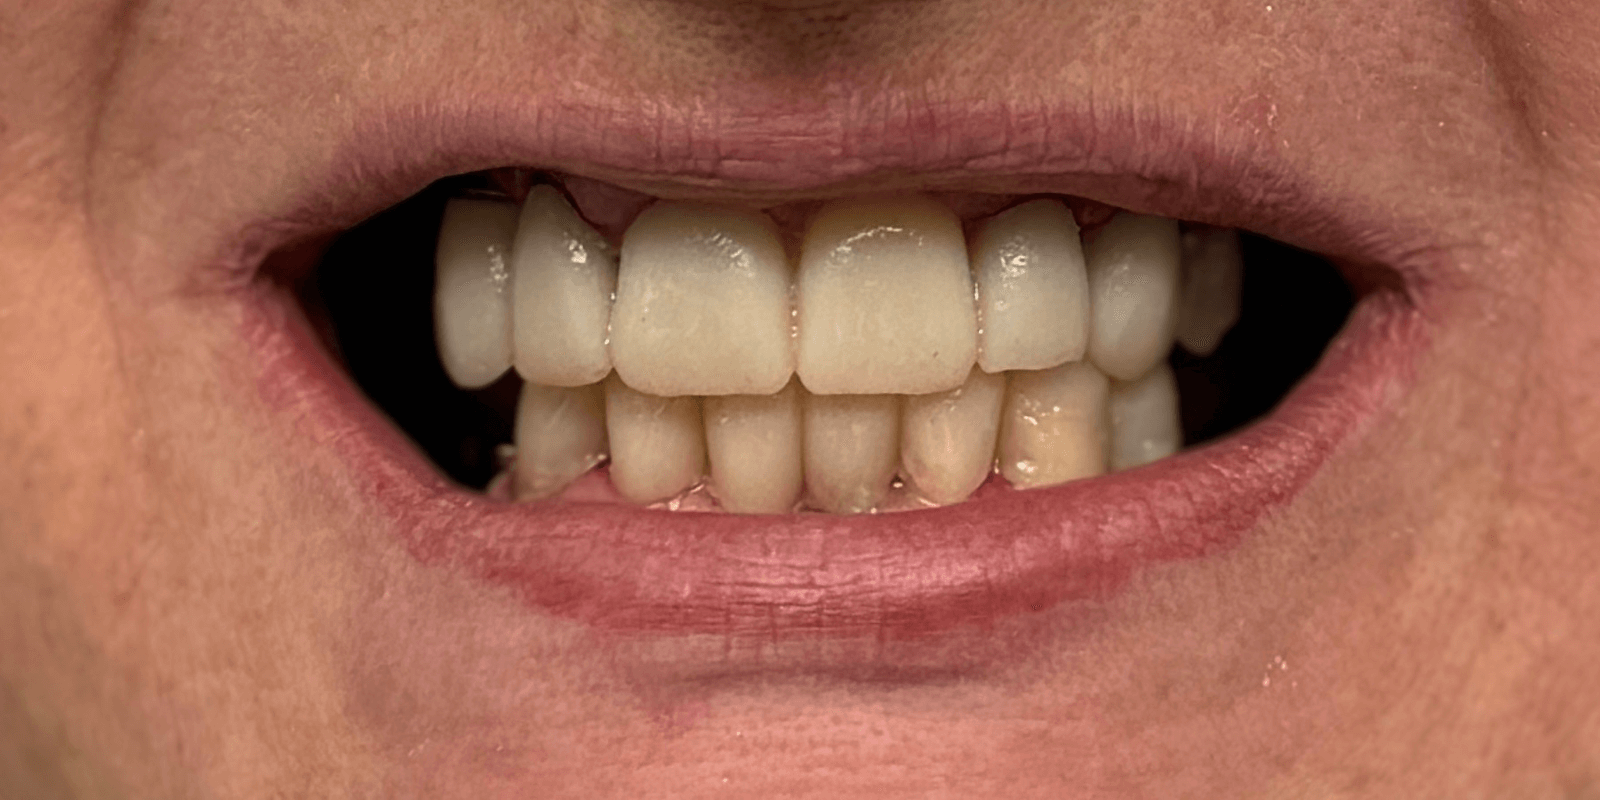

- Ортопедические конструкции изготовить из диоксида циркония, цвет bleach-2.

Итог

С момента первого визита прошло чуть менее трех месяцев. И когда пациентка в последний раз посмотрела в зеркало – мы увидели не просто улыбку. Мы увидели, как человек словно вернулся к себе.